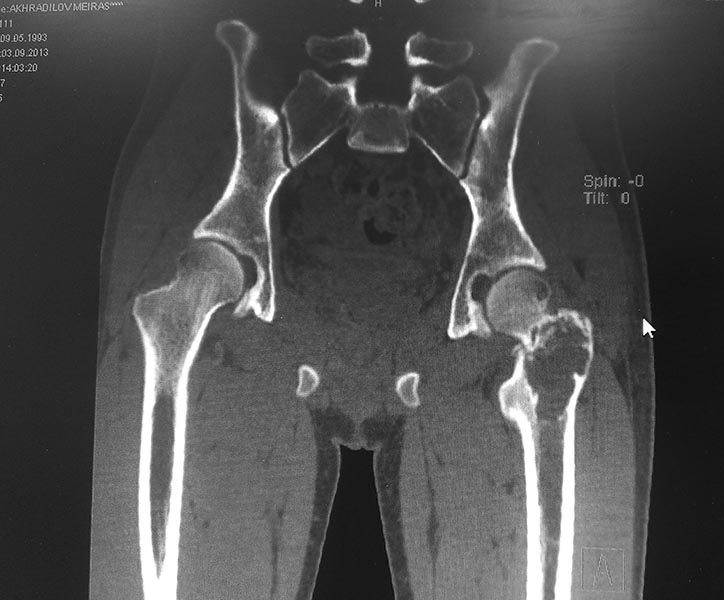

Уважаемые коллеги. Помогите определиться с тактикой лечения. Пациент 1993г.р (20 лет), поступил жалобами :на боли в области левого тазобедренного сустава, нарушение опорной функции левой нижней конечности.Anamnesis morbi: Со слов пациента и медицинской документации 15.08.2013г упал на область левого тазобедренного сустава. По скорой помощи госпитализирован в одну из клиник Астаны, где произведена рентгенография левого тазобедренного сустава, на которой выявлено образование проксимального отдела левой бедренной кости. Для выбора тактики дальнейшего лечение пациента, консультирован остеоонкологом, рекомендовано оперативное лечение в плановом порядке в условиях профильного отделения остеоонкологии АО «РНЦ НМП».Об-но: по внутренним органам без особенностей.Status localis: При осмотре пациент на кровати лежа на спине. Левая нижняя конечность без иммобилизации, ротирована наружу, в области левого тазобедренного сустава отмечается незначительный отек. Осевая нагрузка на левую нижнюю конечность болезненна. При пальпации отмечается резкая боль в области левого тазобедренного сустава. Симптом «прилипшей пятки» отрицательный с обеих сторон. Относительная длина обеих нижних конечностей одинаковая. На периферии конечностей нейроциркуляторных нарушений нет. На представленной R-грамме левого тазобедренного сустава–выявляется деструктивная полость в вертельной области левой бедренной кости нарушение костной структуры с образованием костной полости с тонкостенными перегородками.Границы полости крупно ячеистые. Госпитализирован с предварительным диагнозом: Остеобластокластома вертельной области левой бедренной кости. Закрытый патологический чрезвертельный перелом левой бедренной кости? 04.09.13г 1-м этапом произведена: Операционная биопсия из проксимального отдела левой бедренной кости. Заключение патолого - гистологического исследования: Патоморфологическая картина может соответствовать костной кисте. Пациенту произведено КТ обеих тазобедренных суставов. Заключение: КТ - признаки объемного образования области шейки и большого вертела левой бедренной кости дифференцировать с фиброзной дисплазией. Сростающийся патологический чрезвертельный перелом левой бедренной кости. ОАК, ОАМ, коагулограмма в пределах нормы.